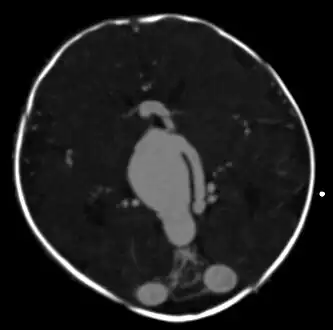

| Large arteriovenous malformation of the parietal lobe | |

An AVM diagnosis is established by neuroimaging studies after a complete neurological and physical examination.[5][11] Three main techniques are used to visualize the brain and search for AVM: computed tomography (CT), magnetic resonance imaging (MRI), and cerebral angiography.[11] A CT scan of the head is usually performed first when the subject is symptomatic. It can suggest the approximate site of the bleed.[3] MRI is more sensitive than CT in the diagnosis of AVMs and provides better information about the exact location of the malformation.[11] More detailed pictures of the tangle of blood vessels that compose an AVM can be obtained by using radioactive agents injected into the blood stream. If a CT is used in conjunctiangiogram, this is called a computerized tomography angiogram; while, if MRI is used it is called magnetic resonance angiogram.[3][11] The best images of an AVM are obtained through cerebral angiography. This procedure involves using a catheter, threaded through an artery up to the head, to deliver a contrast agent into the AVM. As the contrast agent flows through the AVM structure, a sequence of X-ray images are obtained.[11]